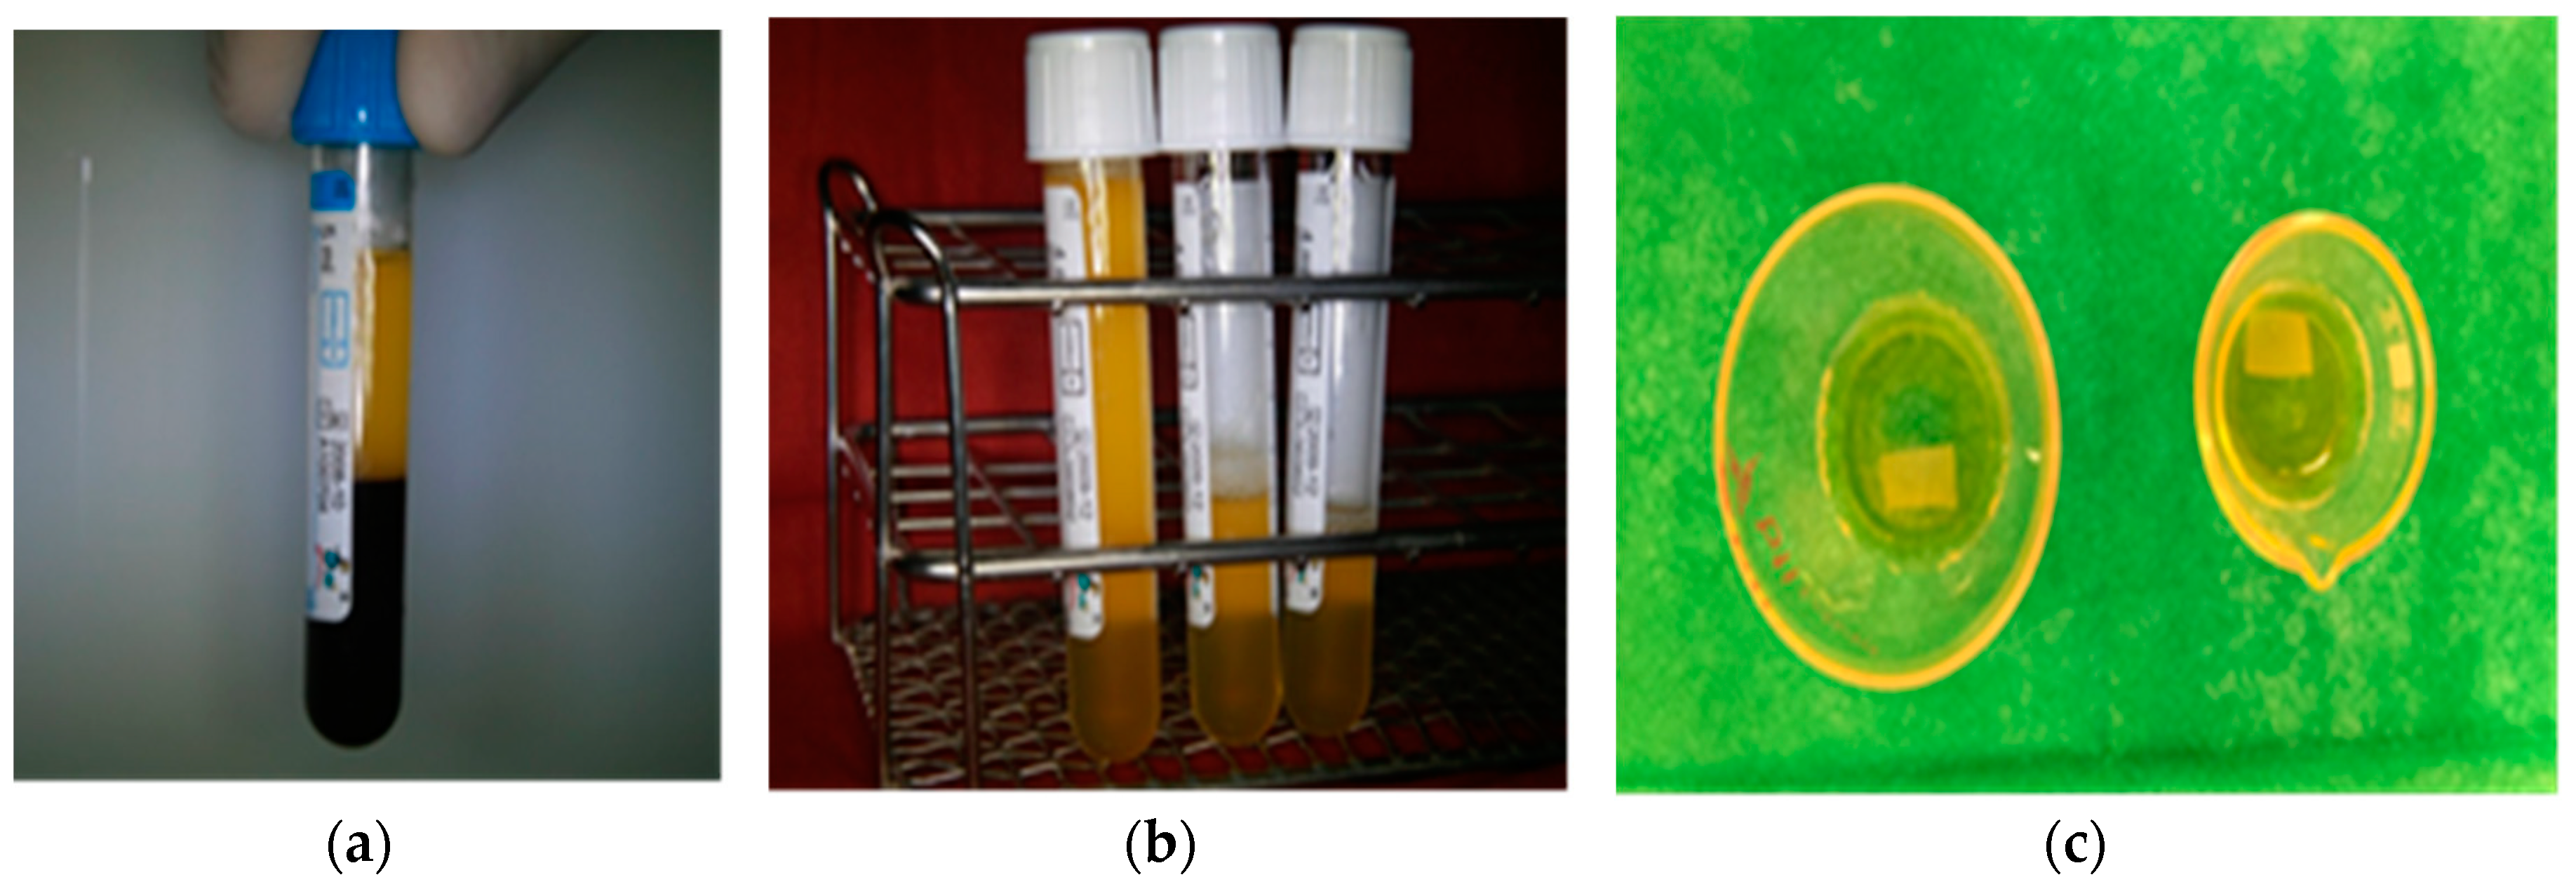

2.1. Preparation of Plasma Rich in Growth Factors (PRGF), Hematology Parameters, and Growth Factor Content

3.1. Preparation of Plasma Rich in Growth Factors (PRGF), Hematology Parameters, and Growth Factor Content